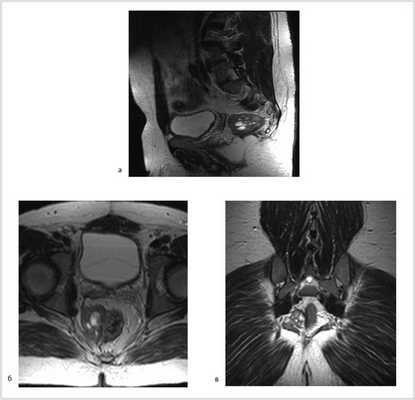

07.11.2012 выполнена цилиндрическая или экстралеваторная экстирпация прямой кишки. Через тазовую брюшину в мезоректальной клетчатке справа пальпируется верхний полюс опухоли, подрастающей к стенке прямой кишки, опухоль фиксирована к правой боковой стенке таза. Отдаленных метастазов нет (рис. 4).

Рис. 4. Этап операции. Ревизия опухоли.

Произведена мобилизация прямой кишки по левой и задней полуокружности, а также пресакрально до мышц тазового дна с соблюдением всех онкологических правил (рис. 5). По левой боковой стенке таза опухолевая капсула интимно прилежит к внутренней подвздошной вене и артерии, острым путем последняя мобилизована от магистральных сосудов.

Рис. 5. Этапы операции. а — мобилизация слева; б — мобилизация справа.

Далее сигмовидная кишка пересечена на уровне ее дистальной трети, а прямая кишка погружена в малый таз, при этом тазовая брюшина ушита над заглушенной культей прямой кишки. Затем сигмовидная кишка забрюшинно выведена в левом боковом отделе живота на переднюю брюшную стенку и сформирована плоская колостома, после чего брюшная полость ушита наглухо послойно (рис. 6).

Рис. 6. Этапы операции. а — ушивание тазовой брюшины; б — сигмостома.

Далее больной перевернут на живот в положении по типу «перочинного ножа» (рис. 7).

Рис. 7. Положение больного на столе (а). Вид операционного поля промежности (б).

После обработки операционного поля мобилизация прямой кишки продолжена из широкого промежностного доступа. Выполнено ушивание заднего прохода кисетным швом, намечены края резекции. В проекции крестцово-копчикового сочленения кожа и подкожная жировая клетчатка рассечены до задней крестцово-копчиковой связки. Последняя пересечена в поперечном направлении. Выполнена ампутация копчика с последовательным пересечением передней крестцово-копчиковой и крестцово-прямокишечной связок (рис. 8).

Рис. 8. Этапы операции. а — ушивание ануса; б — рассечение кожи и подкожной жировой клетчатки; в — пересечение крестцово-копчиковых связок.

Далее прямая кишка с опухолью в едином блоке мобилизована острым путем от предстательной железы и правой стенки таза, после чего выполнена цилиндрическая брюшно-промежностная экстирпация прямой кишки. Малый таз дренирован двумя силиконовыми дренажами и ушит наглухо (рис. 9).

Рис. 9. Этапы операции. а — мобилизация простаты; б — дренирование малого таза; в — конечный вид раны.

Гистологическое заключение: в жировой клетчатке прямой кишки, с учетом иммуногистохимического исследования разрастания злокачественной гемангиоперицитомы с признаками лечебного патоморфоза 1-й степени (жизнеспособной опухолевой ткани более 50% по DWORAK). Опухоль не прорастает в прилежащий мышечный слой кишки. В одном лимфатическом узле прилежащей клетчатки элементов опухолевого роста нет. В краях резекции кишки без элементов опухолевого роста. Под маркировкой «латеральный край опухоли» — кусочек фиброзной ткани с очагами ксантоматоза (рис. 10).

Рис. 10. Макропрепарат.

Продолжительность операции составила 3 ч 30 мин, кровопотеря — 500 мл. Интраоперационных и ранних послеоперационных осложнений не было. Пациент на 12-е сутки выписан из хирургического отделения.